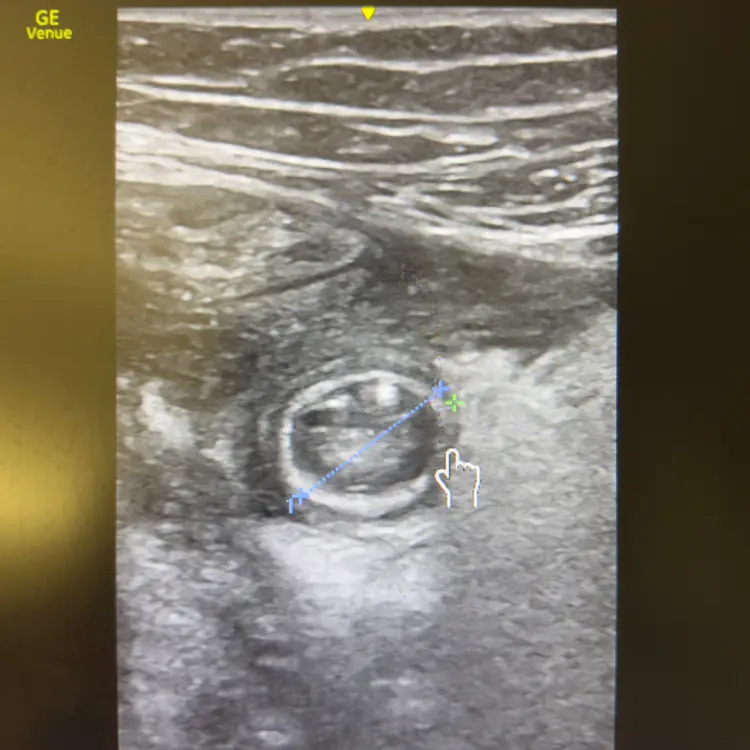

Globe ou obstruction : trancher en urgence.